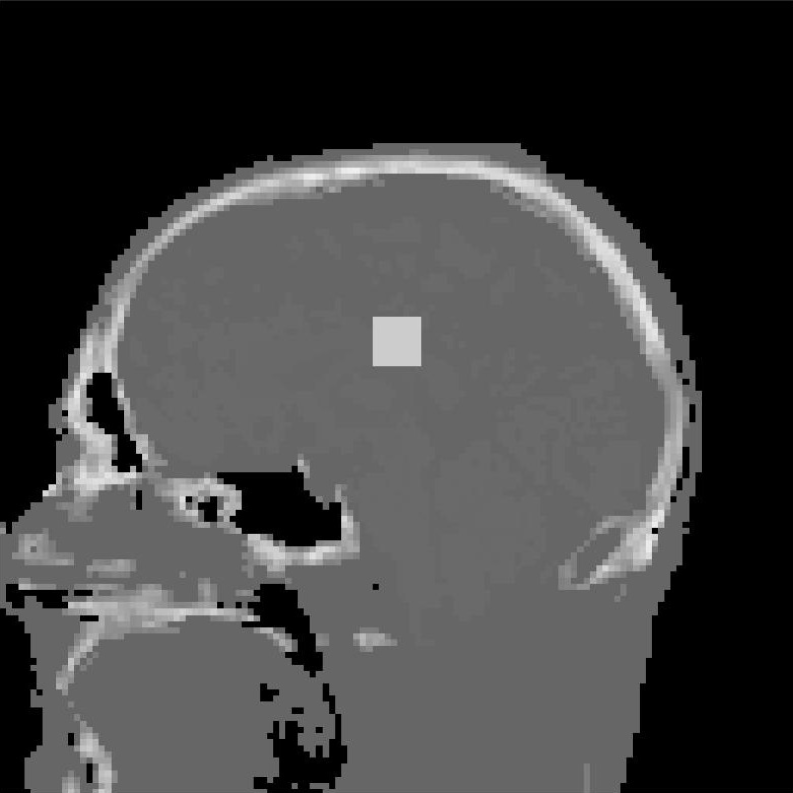

3.1 Digital Head Phantom

In this synthetic example we consider cases where we want to assess if potential tumours have appeared (or changed in size or shape), using a very low number of projections, and we report reconstruction accuracy and computational time for different choices of regularization and optimization algorithm. In particular, we consider a digital head phantom, of size 128×128×128128\times 128\times 128 voxels, with a (synthetically) added cubic tumour of 8×8×88\times 8\times 8 voxels. The DRRs projections were computed in TIGRE with resolution 128×128×20128\times 128\times 20 projections. Note that this is a heavily undersampled dataset: we only consider 20 projections in each imaging step, while a standard clinical scan would require on the order of 600 projections. Even if this is a simple example, i.e. it is highly unlikely to observe a cubic tumour in practice, we believe this to be a highly illustrative test scenario, in which we can both asses the reconstruction quality of the fine structure in the digital head phantom, as well as the edges of the tumour.

For all the algorithms including prior image regularization, the head phantom image without the tumour was used as prior image. This is a reasonable choice, since we know we can do a high-dose scan once and obtain a very accurate reconstruction. Moreover, since this is a synthetic example, we can use the true solution as the ground truth image in our quantitative analysis.

Figure 1 exhibits a slice of the reconstructed images using all the aforementioned algorithms. Here, (a) is the prior image 𝒙p\boldsymbol{x}_{p}, (f) is the ground truth, and the rests are the reconstructed images (top) with the corresponding reconstructions errors (bottom), all displayed using the same colorbar. Note that the error is just the difference between the reconstruction with respect to the ground truth image, so that high pixel intensity indicates inaccurate reconstructions and a fully black image would indicate a perfect reconstruction. This local error information is more informative than only displaying the error norms, or global error, since one can easily observe there is a high local difference between reconstructions.